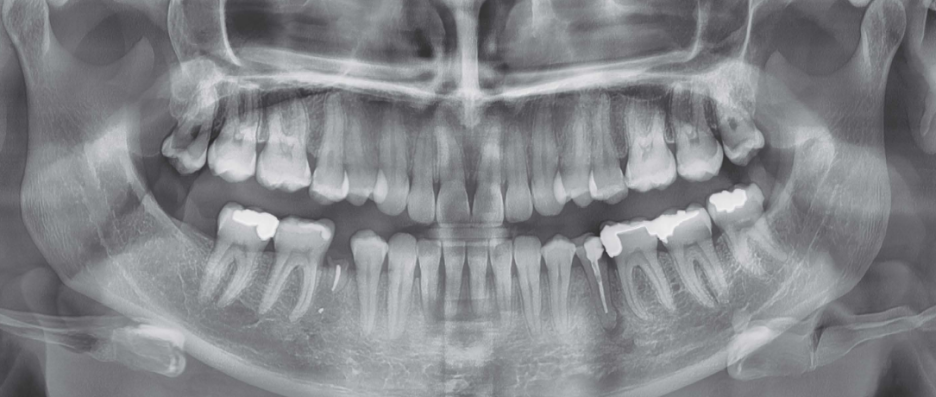

치아 진단 의료기기 관련주, 바텍 주가 전망 Feat. 글로벌탑티어

(1) CNT X-ray, 독보적 기술 우위, 산업용 검사 X-ray 기대감 ↑

CNT는 X-ray 촬영 선원을 아날로그 방식(열전자 기반)에서 디지털로 변환한 혁신 기술인데, CNT를 적용하면 기존 아날로그 튜브보다 크기와 무게를 줄여 초경량 엑스레이 장비에 적용해 고해상도 영상을 획득할 수 있다.

이로써 X-ray 선량을 디지털로 마이크로세컨드 단위까지 조절할 수 있어 인체에 노출되는 방사선량도 줄였기에 시장에서 반응이 뜨거운 것이다.

치과의 디지털 전환이라는 패러다임 변화에 가장 적합한 장비라는 인식되면서 최근 구강스캐너 시장이 빠르게 성장하고 있다. 고령화가 가속화되면서 헬스케어 관심이 높아지고, 치아건강 중요성도 인식되고 있기 때문이다.